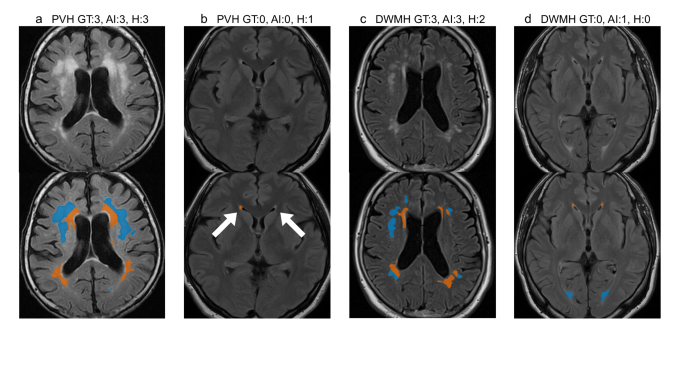

Figure 2 illustrates the Fazekas scale grading results. The top row displays the original slices, whereas the bottom row highlights the AI-predicted PVH (orange) and DWMH (blue) regions, with subtitles indicating the corresponding grades. AI predictions were determined using thresholds derived from the Youden-neighbor method.

Fazekas scale grading results of representative patients. The top image displays a representative slice from an MRI volume, whereas the bottom image shows AI-predicted PVH (orange) and DWMH (blue) regions for the same slice. Titles indicate grading results (PVH or DWMH) for the entire volume: ground truth grade, AI-predicted grade, and human expert-predicted grade. (a) A patient for whom both the AI and the human expert graded correctly. (b) A patient for whom only the AI graded PVH correctly. (c) A patient for whom only the AI graded DWMH correctly. (d) A patient for whom the AI failed in DWMH grading, whereas the human expert’s grade was accurate.

Figure 2a presents representative successful cases where both the AI and human experts accurately predicted grades, demonstrating PVH and DWMH separation based on a fixed distance from the lateral ventricles. Figure 2b shows that the AI correctly predicted a PVH grade of 0, whereas the human expert overestimated it as grade 1. The AI detected small PVH regions (indicated by white arrows) but classified them as grade 0, as their volume ratio fell below the threshold. Figure 2c illustrates a case in which the AI accurately predicted a DWMH grade of 3. Figure 2d depicts a case in which the AI failed in DWMH grading, whereas the human expert’s grade was accurate. In this case, the boundary between PVH and DWMH was ambiguous; the AI applied consistent, distance-based rules to make definitive judgments from the ventricular surface. For DWMH grading, although the Fazekas scale provides a qualitative definition, the AI made quantitative decisions based on volume ratios and learned thresholds.

In this study, AI-based grading demonstrated lower performance for DWMH compared with PVH in terms of accuracy, F1-score, MAE, and inter-rater agreement. Several factors may account for this discrepancy. First, the discrepancy may stem from both pathophysiological and definitional differences. PVH is spatially well-defined by its proximity to the ventricles, allowing more consistent interpretation and algorithmic learning. By contrast, DWMH lesions are heterogeneous in shape, location, and signal intensity, often appearing as scattered or confluent foci, which complicates segmentation and classification. Moreover, the Fazekas grade 2 definition—“beginning of confluence”—emphasizes spatial proximity rather than total volume, a feature not fully captured by the volume-based thresholds used in the AI algorithm, potentially leading to boundary misclassifications. When the posterior horn of the lateral ventricle is minimally visible, WMHs in that region are often intuitively interpreted as PVH by human experts. However, as our algorithm strictly classifies WMHs based on distance from the ventricle, these lesions tend to be labeled as DWMH instead (Fig. 2d). Second, as illustrated in Fig. 1a, DWMH volume on the Brain Dock scale increases sharply from grade 2 to grade 3, whereas PVH volume rises more gradually across all grades. This contrast likely reflects differences in the scale definitions. Grade 2 DWMH (“mottled lesions ≥ 3 mm in diameter”) can be satisfied by only a few small lesions, resulting in a relatively low total volume, whereas grade 3 DWMH (“confluent foci in deep white matter”) requires lesion confluence, producing a sudden volumetric surge. By contrast, grade 2 PVH (“extending throughout the periventricular area”) already encompasses the entire ventricular border, and grade 3 PVH (“extending into deep white matter”) represents deeper extension rather than wider spread, yielding more modest volume changes. This abrupt volumetric shift contributes to classification instability, whereby minor discrepancies near the grade boundary may result in misclassification and higher MAE. These findings suggest that a volume-based classification method may be particularly suitable for evaluating DWMH. Third, DWMH is more susceptible to inter-rater variability among expert neuroradiologists compared with PVH, suggesting that the reliability of ground truth labels for DWMH may be inherently lower41. This variability can introduce noise during model training, potentially impairing the generalization performance of the AI model and reducing its F1-score.